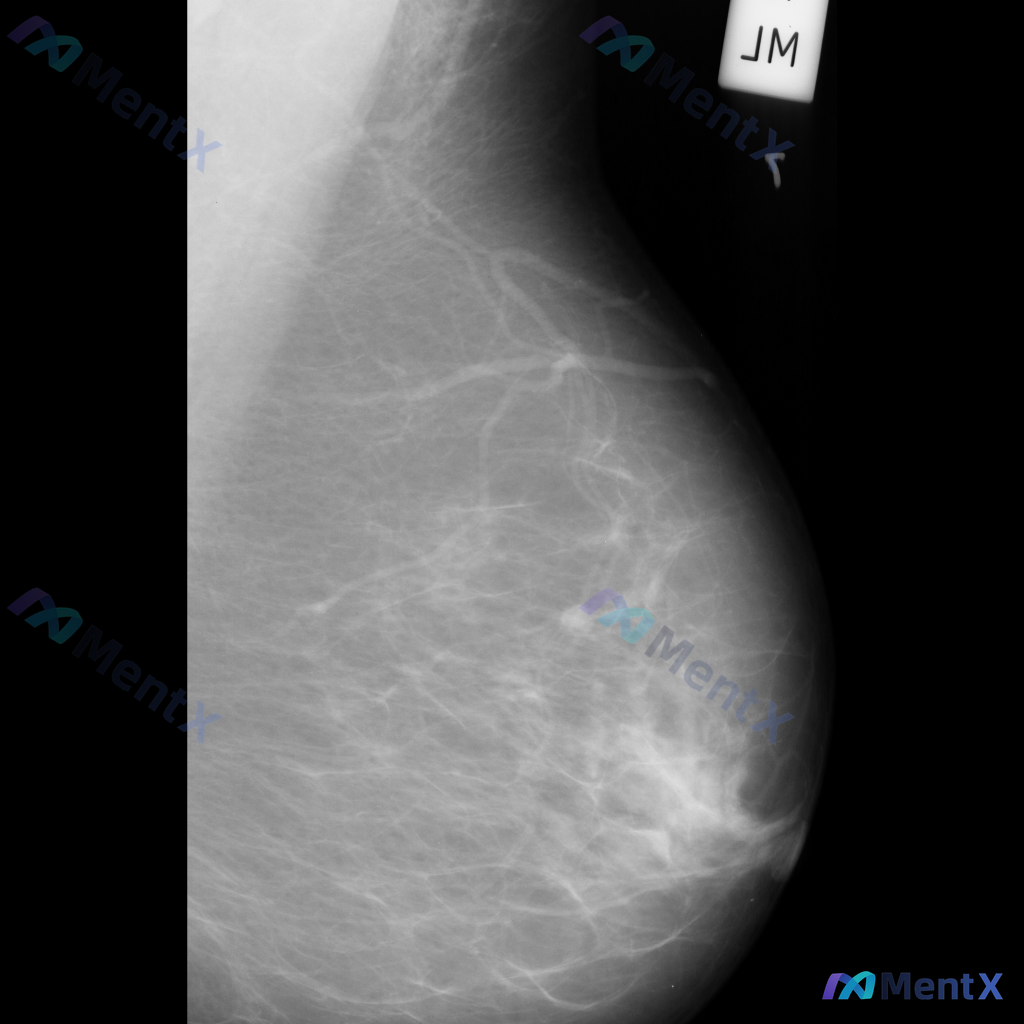

整理到一张单张乳腺钼靶的影像资料,大家可以一起看看: 影像里主要能看到这些表现: 1. 乳腺上部区域,沿血管走行分布有线样结构伴条索状和点状钙化; 2. 乳腺实质内部,散在分布着一些粗大斑片状/粗棒状钙化,边缘相对清晰、密度比较高; 3. 乳腺中下部区域,还能看到数个小的、边缘相对清晰的圆形或卵圆形...